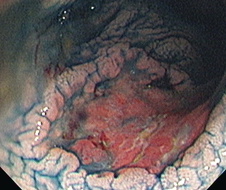

- People with ulcerative colitis and Crohn's colitis have a 2-3x increased colorectal cancer (CRC) risk (on average) compared to the general population

- Surveillance for CRC in IBD is fraught with challenges - there is a much higher Post Colonoscopy Colorectal Cancer (PCCRC) rate in IBD compared to the general population as there is an increased difficulty in detecting and resecting these lesions, as well as an accelerated cancer biology

- Important - high clinical consequence - make a mistake, and your patient may be subjected to unnecessary life-changing surgery or an avoidably high lifetime risk of cancer